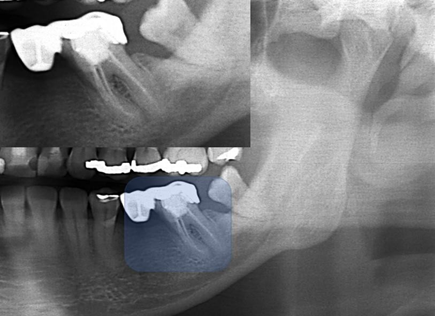

Radiographic images compatible with excess or lack of restorative material was the most common iatrogenesis in the analyzed images (61.57%), followed by insufficient endodontic treatment (26.27%) where findings of lack of obturator material, apical obturation below were found beyond the radiographic apex. Also, 74 (12.16%) radiographs showed two or more types of iatrogenesis Figure 1 & 2.

Figure 1 Interproximal radiography of the Molares D region, diagnosed on panoramic radiography. The arrow points to the distal of tooth 16, showing excess of the prosthetic crown, that causes iatrogeny.

Figure 3Interproximal radiography of the molars and premolars D region, diagnosed on panoramic radiography. The arrows point to the distal of tooth 45, showing excess of amalgam restoration, in the distal box, which characterize iatrogeny. Note that the alveolar bone crest is already in the process of resorption.

Figure 4 Periapical radiography of the molars and lower premolars region D. There is a fixed prosthesis with three elements, teeth 45 and 47 being pillars. Suspended element 46. Note the lack of material in the distal of tooth 45 and the excess in the mesial of the tooth 47, which characterize iatrogeny. Both teeth are treated endodontically. The endodontic treatment of teeth 44 and 45 is correct, apparently.